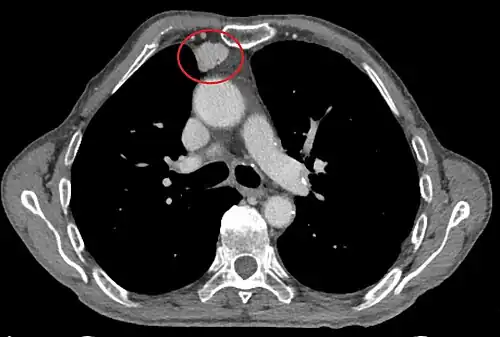

Les critères scanographiques d'envahissement local doivent être recherchés car ils guideront le traitement. D'autre part, l'envahissement scanographique est corrélé au pronostic[30]. L'absence d'un liseré graisseux entre la masse et les vaisseaux, notamment l'aorte et la veine cave supérieure, est un signe d'envahissement local. L'ascension d'une coupole diaphragmatique, comme en radiographie thoracique, est un signe d'envahissement du nerf phrénique[31].

Présentation tomodensitométrique classique d'un thymome à un stade précoce (cercle rouge). À l'arrière, l'aorte, la veine cave supérieure et l'artère pulmonaire sont visibles en coupe.